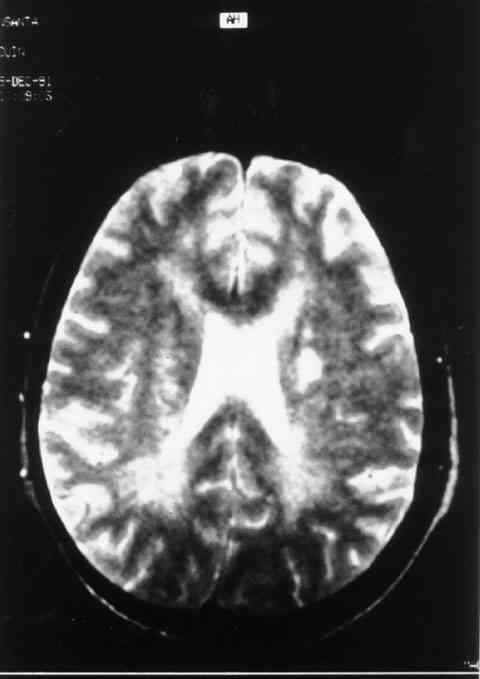

Figura 1

LESIONES DESMIELINIZANTES EN SUSTANCIA BLANCA DE AMBOS HEMISFERIOS, DE PREDOMINIO PERIVENTRICULAR.